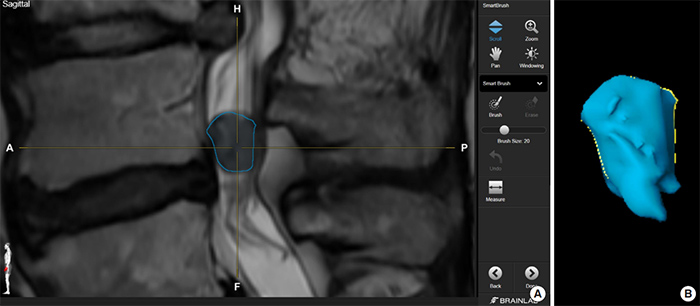

(A) Highlighting of the neoplasm on a preoperative MRI software (B) “Smartbrush” function of the software automatically renders the 2-dimensional highlighting on the MRI into a 3-dimensional shape (Credit: Neurospine, September 2022)